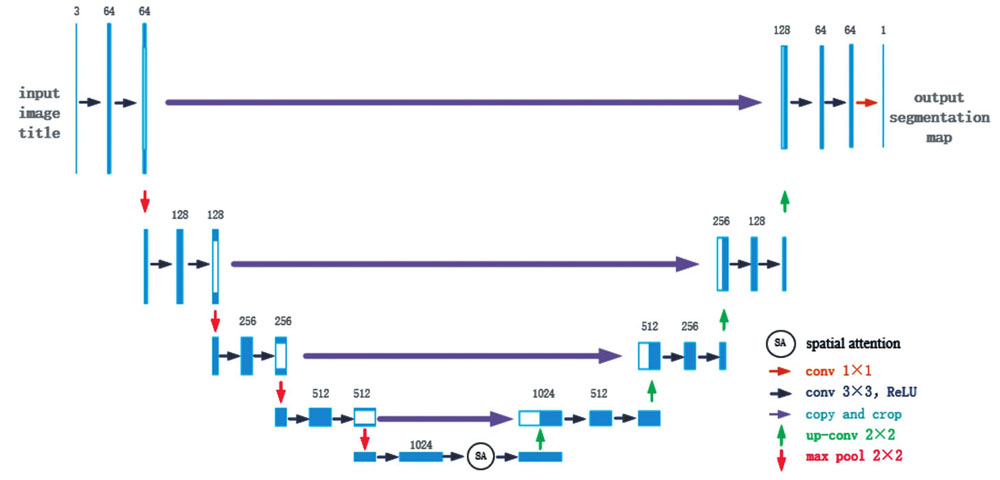

U-net网络是2015年由Ronneberger等[17]在FCN的基础上提出的一种典型的语义分割网络,其结构如

从

在扩张路径上,U-net网络配置了大量的特征图通道,能让最终复原的分割图像保留丰富的输入信息。每一个步骤包含一个特征图上采样和一个2×2的上卷积,使通道数减半,然后是复制和裁剪,把收缩路径中相同层的特征图经过裁剪之后拼接在当前层(由于左侧路径中的特征图比右侧对应路径中的特征图要大一些,因此需要裁剪之后才能做拼接),接着是两个3×3卷积和修正线性单元。在最后一个层,使用1×1卷积将64元素的特征向量映射到不同的类别。这样的U-net网络共有23个卷积层。这种结构设计可以有效提取图像的细节信息,故有利于其在医学图像语义分割方面的应用。但处理人体口腔图像这种复杂图像时,常规U-net的识别效果已难以满足要求。

为了提高算法的识别效果,本文改进了原始的U-net网络,调整了U-net网络参数并引入了空间注意力机制[21]。空间注意力机制是一种模拟人类的思维进行设计的优化方案,其核心思想是依据贡献值对资源进行再分配。本文引入该机制是为了改善神经网络的权重问题。由于研究目的是分割出牙齿,故引入空间注意力机制以改变图像不同区域的权重值,相关性高的区域会拥有更高的权重,使任务需要的目标区域更为突出,算法有更好的识别效果。

加入空间注意力机制模块并调整了网络参数后,经过改进的U-net网络的结构如